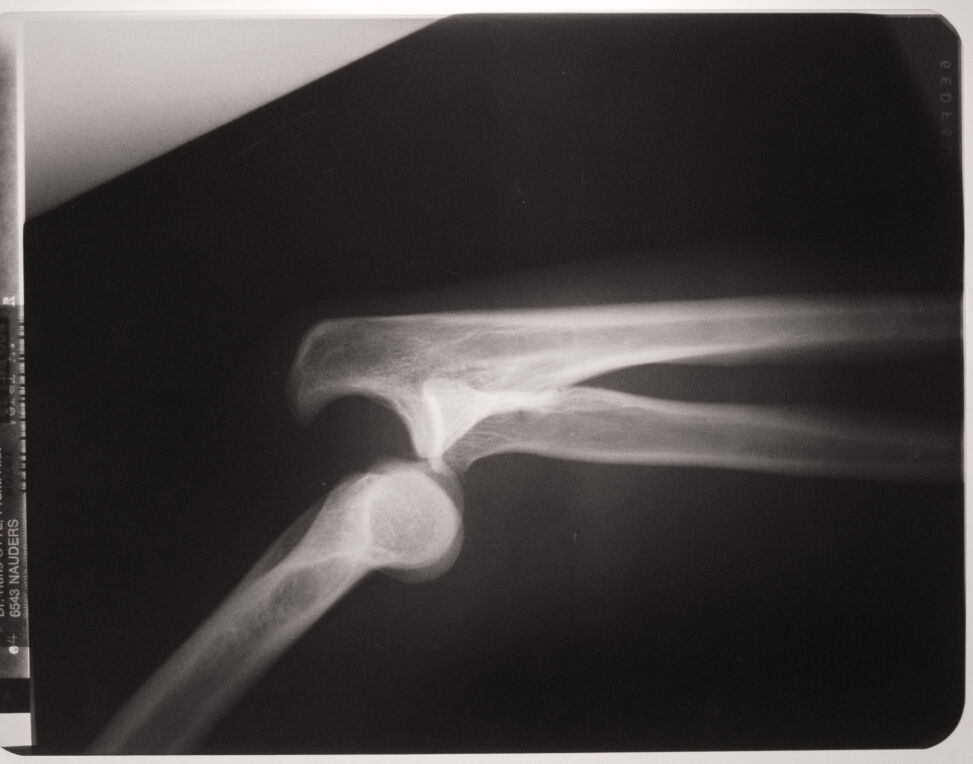

Can You Use A Dislocated Arm. A dislocation is when the ball and socket joint of the shoulder is disrupted. The shoulder joint is made up of your upper arm bone (the. Web while best done by a medical professional, you can learn how to fix a dislocated shoulder on your own should you find yourself isolated or otherwise unable to access care. The process of popping a dislocated shoulder back into place is called reducing the shoulder. Web an unexplained pain in your shoulder can mean a number of things. Here's how to identify a dislocated shoulder and what to do about it. Web never try to pop your shoulder back in place on your own. Don’t let anyone other than a healthcare provider touch or move it. Web advice after dislocating your shoulder joint. If it is dislocated, a doctor will rotate your arm back into place. A dislocated shoulder occurs when the top part of the upper arm bone partially or fully comes out of the socket. What to expect from your doctor.